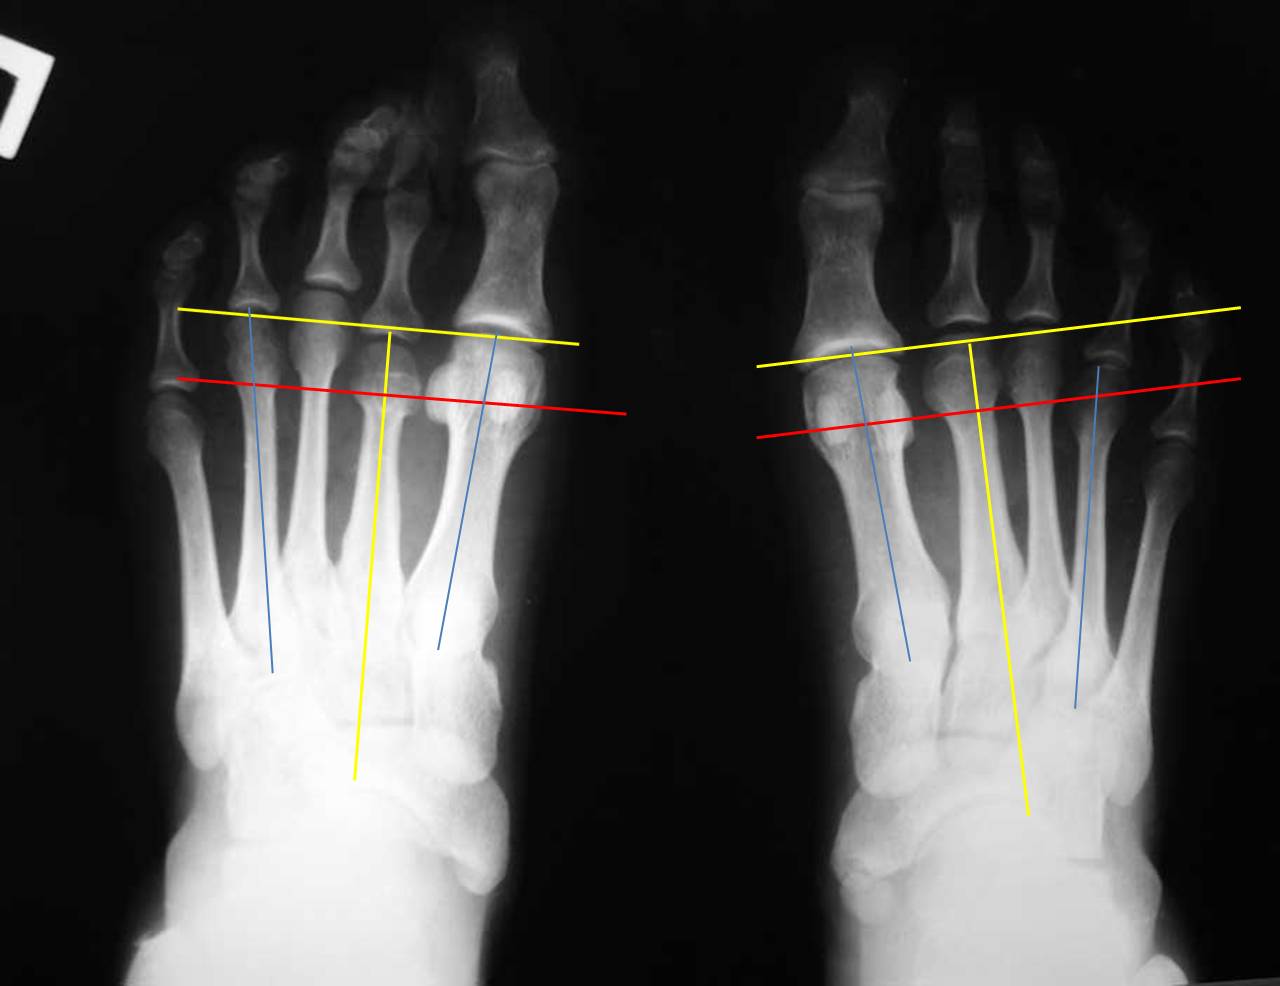

Я провел несколько ориентиров на представленных рентгенограммах, чтобы показать разницу в биомеханических ситуациях. На левой стопе перпендикуляр, проведенный к оси 2 плюсневой кости через дистальный конец 1 плюсневой (желтые линии) (принято за ориентир брать ось 2 плюсневой кости) проходит через верхушки 2 и 3 плюсневых. В нормальной ситуации 2 плюсневая кость должна быть чуть длинее 1-й. То есть на левой стопе можно говорить об относительно длинной 1 плюсневой кости. Именно этим объясняется наличие у молодой женщины признаков артроза 1 плюснефалангового сустава. А вот длина 4 плюсневой кости на левой стопе нормальная: перпендикуляр к оси 2 плюсневой проходит через середину латеральной сесамовидной кости и середину головки 4 плюсневой (красная линия). Теперь посмотрите на правую стопу: 3-я плюсневая кость намного длинее 1-й, а 4-я такой же длины. Такого в норме никак не может быть. А вот вторая при правильной разметке оказывается совсем чуть чуть короче первой. При этом абсолютная длина 1-й плюсневой (в милиметрах) у меня получилась на левой стопе даже больше, а длина 4 плюсневой на правой стопе на 4мм больше, чем на левой (голубые линии). Вот и получается, что на правой стопе наряду с небольшим укорочением 2 плюсневой есть более значимое относительное удлинение 3 и 4 плюсневых. И это в перспективе может быть причиной центральной метатарсалгии. Но пока жалобы пациентки связаны только с молоткообразной деформацией 2 пальца, лечение должно быть направлено на ее устранение наименее травматичным способом.

Я не зря задал такой вопрос о НОРМЕ именно для конкретной больной. Хотя, как Вы правильно подметили, я не очень знаком «с понятием формулы, или взаимоотношений длин плюсневых костей, которые определяют равномерность нагрузки на передний отдел стопы», но я знаю, что существует три типа взаимоотношений длин плюсневых костей на НОРМАЛЬНОЙ стопе: index minus type, index plus-minus type and index plus type (H. T. Kim, S. H. Lee, C. I. Yoo, J. H. Kang, J. T. Suh. The management of brachymetatarsia//J Bone Joint Surg [Br] 2003;85-B:683-90). В этой же статье и рисунок 2 есть, посмотрите эти типы НОРМЫ. Поэтому то, что Вы нарисовали ( отношение 1 и 2 плюсневых костей на левой стопе) является нормой, а Вы утверждали обратное. Поэтому я считаю, что для данной конкретной больной взаимоотношение плюсневых костей является НОРМОЙ, от чего и надо отталкиваться при сравнении длины плюсневых костей на обеих стопах. Да, я с Вами согласен, что по сравнению с левой стопой на правой удлинены 3-5 плюсневые кости на 2-3 мм, что не считается патологией. Равномерное и незначительное удлинение плюсневых костей (на 2-3 мм) не является патологией. Вы со мной согласны? Да, головка 5 плюсневой кости по отношению к головке 4 плюсневой кости на левой стопе на 2-3 мм стоит выше, чем на правой. Головка 4 плюсневой кости по отношению к 3-й плюсневой кости на левой стопе стоит на 3 мм выше, чем на правой. НО, САМОЕ ГЛАВНОЕ – головка 3 плюсневой кости по отношению к головке 2 плюсневой кости на левой ( нормальной) стопе стоит где-то на 3-4 мм выше головки 2 плюсневой кости, а на правой ( больной) стопе головка 3 плюсневой кости по отношению к головке 2 плюсневой кости стоит выше АЖ на 17 мм. Это Вы считаете НОРМОЙ? Это, по-Вашему, не считается брахиметатарсией? Brachymetatarsia is diagnosed when one metatarsal ends 5 mm or more proximal to the parabolic arc(H. T. Kim, S. H. Lee, C. I. Yoo, J. H. Kang, J. T. Suh. The management of brachymetatarsia//J Bone Joint Surg [Br] 2003;85-B:683-90). А в нашем случае разница АЖ в 13-14 мм по сравнению с плюсневой формулой на левой-нормальной стопе.

Теперь об укорочении 1 пальца. Вы же сами вполне справедливо отметили, что даже в абсолютной величине на левой стопе 1 плюсневая кость длиннее подобной же кости на правой – больной стопе. Плюс ко всему, на Вашем, профессионально расчерченном рисунке, можно четко увидеть, что расстояние между головками 1 и 3 плюсневых костей на левой стопе – 0 мм, а на правой-больной стопе – МЕНЬШЕ АЖ на10 мм. То есть 1 плюсневая кость на больной стопе по отношению к нормальной параболе плюсневых костей УКОРОЧЕНА. О чем я и говорил, а Вы почему-то возражали.